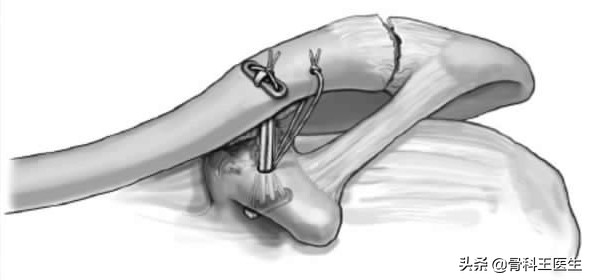

2、用锚钉也可以把锁骨拉下去,因为有的锚钉X线不能显示,所以用示意图: